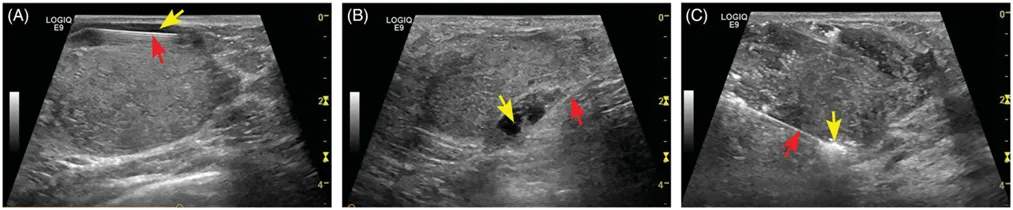

收集2013年2月至2018年12月在介入超聲科就診的女性患者,她們有可能與乳房病變有關的局部疼痛、不適或壓迫癥狀。納入標準:(a)經穿刺活檢病理證實為乳腺良性病變;(b)超聲檢查最大病變直徑≥2.0cm;(c)因合并癥而不適合手術切除或因美容問題而拒絕接受手術;(d)年齡在18-60歲之間。排除標準:(a)有凝血功能障礙或嚴重心肺疾病的患者;(b)急性或活動性感染患者;(c)懷孕、哺乳或月經期的患者。所有患者在治療前均接受超聲成像測量三個垂直直徑(a-左至右,b-前至后,c-上至下的直徑),并計算病變體積V = 0.525* (a*b *c)(a-左至右,b-前至后,c-上至下的直徑)。消融前在結節(jié)周圍進行局部麻醉,為避免痛覺過敏患者的疼痛,保護正常組織免受熱損傷,采用了水隔離技術。即消融前,超聲引導下在結節(jié)邊緣與鄰近皮膚、胸肌或乳暈之間的部位注射10-30ml生理鹽水,實現水隔離,如Fig1。使用20W和30W的功率進行消融,對于血管豐富的部分,消融針移動速度較慢,輸出功率為30W。手術后,在消融的區(qū)域放置冷敷袋兩小時。術后患者在觀察室接受半小時的健康監(jiān)測。

Fig1 超聲引導下水隔離影像圖。(A - B)首先用細針(紅色箭頭)在結節(jié)區(qū)與皮膚(A)、結節(jié)區(qū)與胸肌(B)之間注入液體(黃色箭頭)。(C)水隔離成功后,將MWA針置于結節(jié)底部(紅色箭頭)。然后在MWA開始時,消融區(qū)(黃色箭頭)的高回聲度逐漸增加。